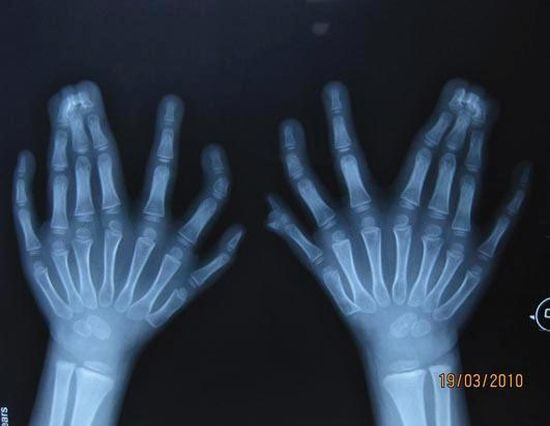

Radiografii terifiante: foarfece in cap, cuie in gat si furculite in mana

Surublenite infite in cap, plamani "dotati" cu cuie sau laringe "presarat" cu foarfece. Sunt numai cateva dintre cele mai ingrozitoare radiografii cu care s-au confruntat medicii de-a lungul timpului.

Fie ca a fost vorba despre accidente sau malformatii, de oamenii sau animale, cu siguranta "perfomentele" lor i-au lasat cu gura cascata pe medici.

Iata mai jos o serie cu unele dintre cele mai "spectaculoase" radiografii.